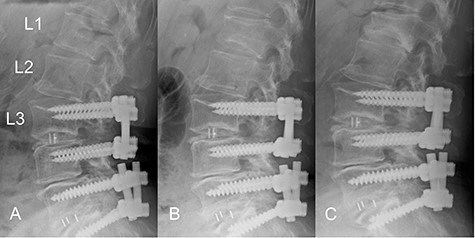

Time course of a vertebral fracture at L1. (A) Radiographic image obtained just before the vertebral fracture occurred. (B) The vertebral fracture had occurred at L1 4 months before surgery. (C) Radiographic image obtained when the patient presented with symptoms of radiculopathy shows no apparent posterior slip of the L2 vertebra. The L1 vertebral body was deformed into a wedge shape.